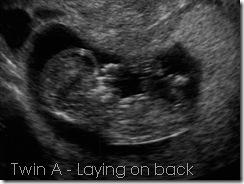

Several of you lovely folks out there have posted the Christmas Meme and I have loved it. I thought I would use it for today. I hope you are having a good day with those you love the most, because really that’s all that ever matters. The sun is shining through my window, the color is so radiant and golden and warm. Today I am at 14 weeks -- 2nd Trimester. I love you my monsters.